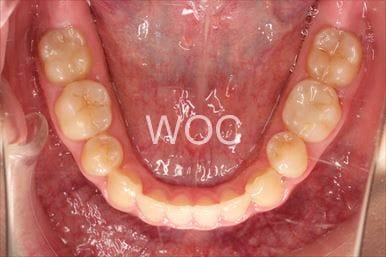

治療中1

治療中2

治療中3

治療中4

治療中5